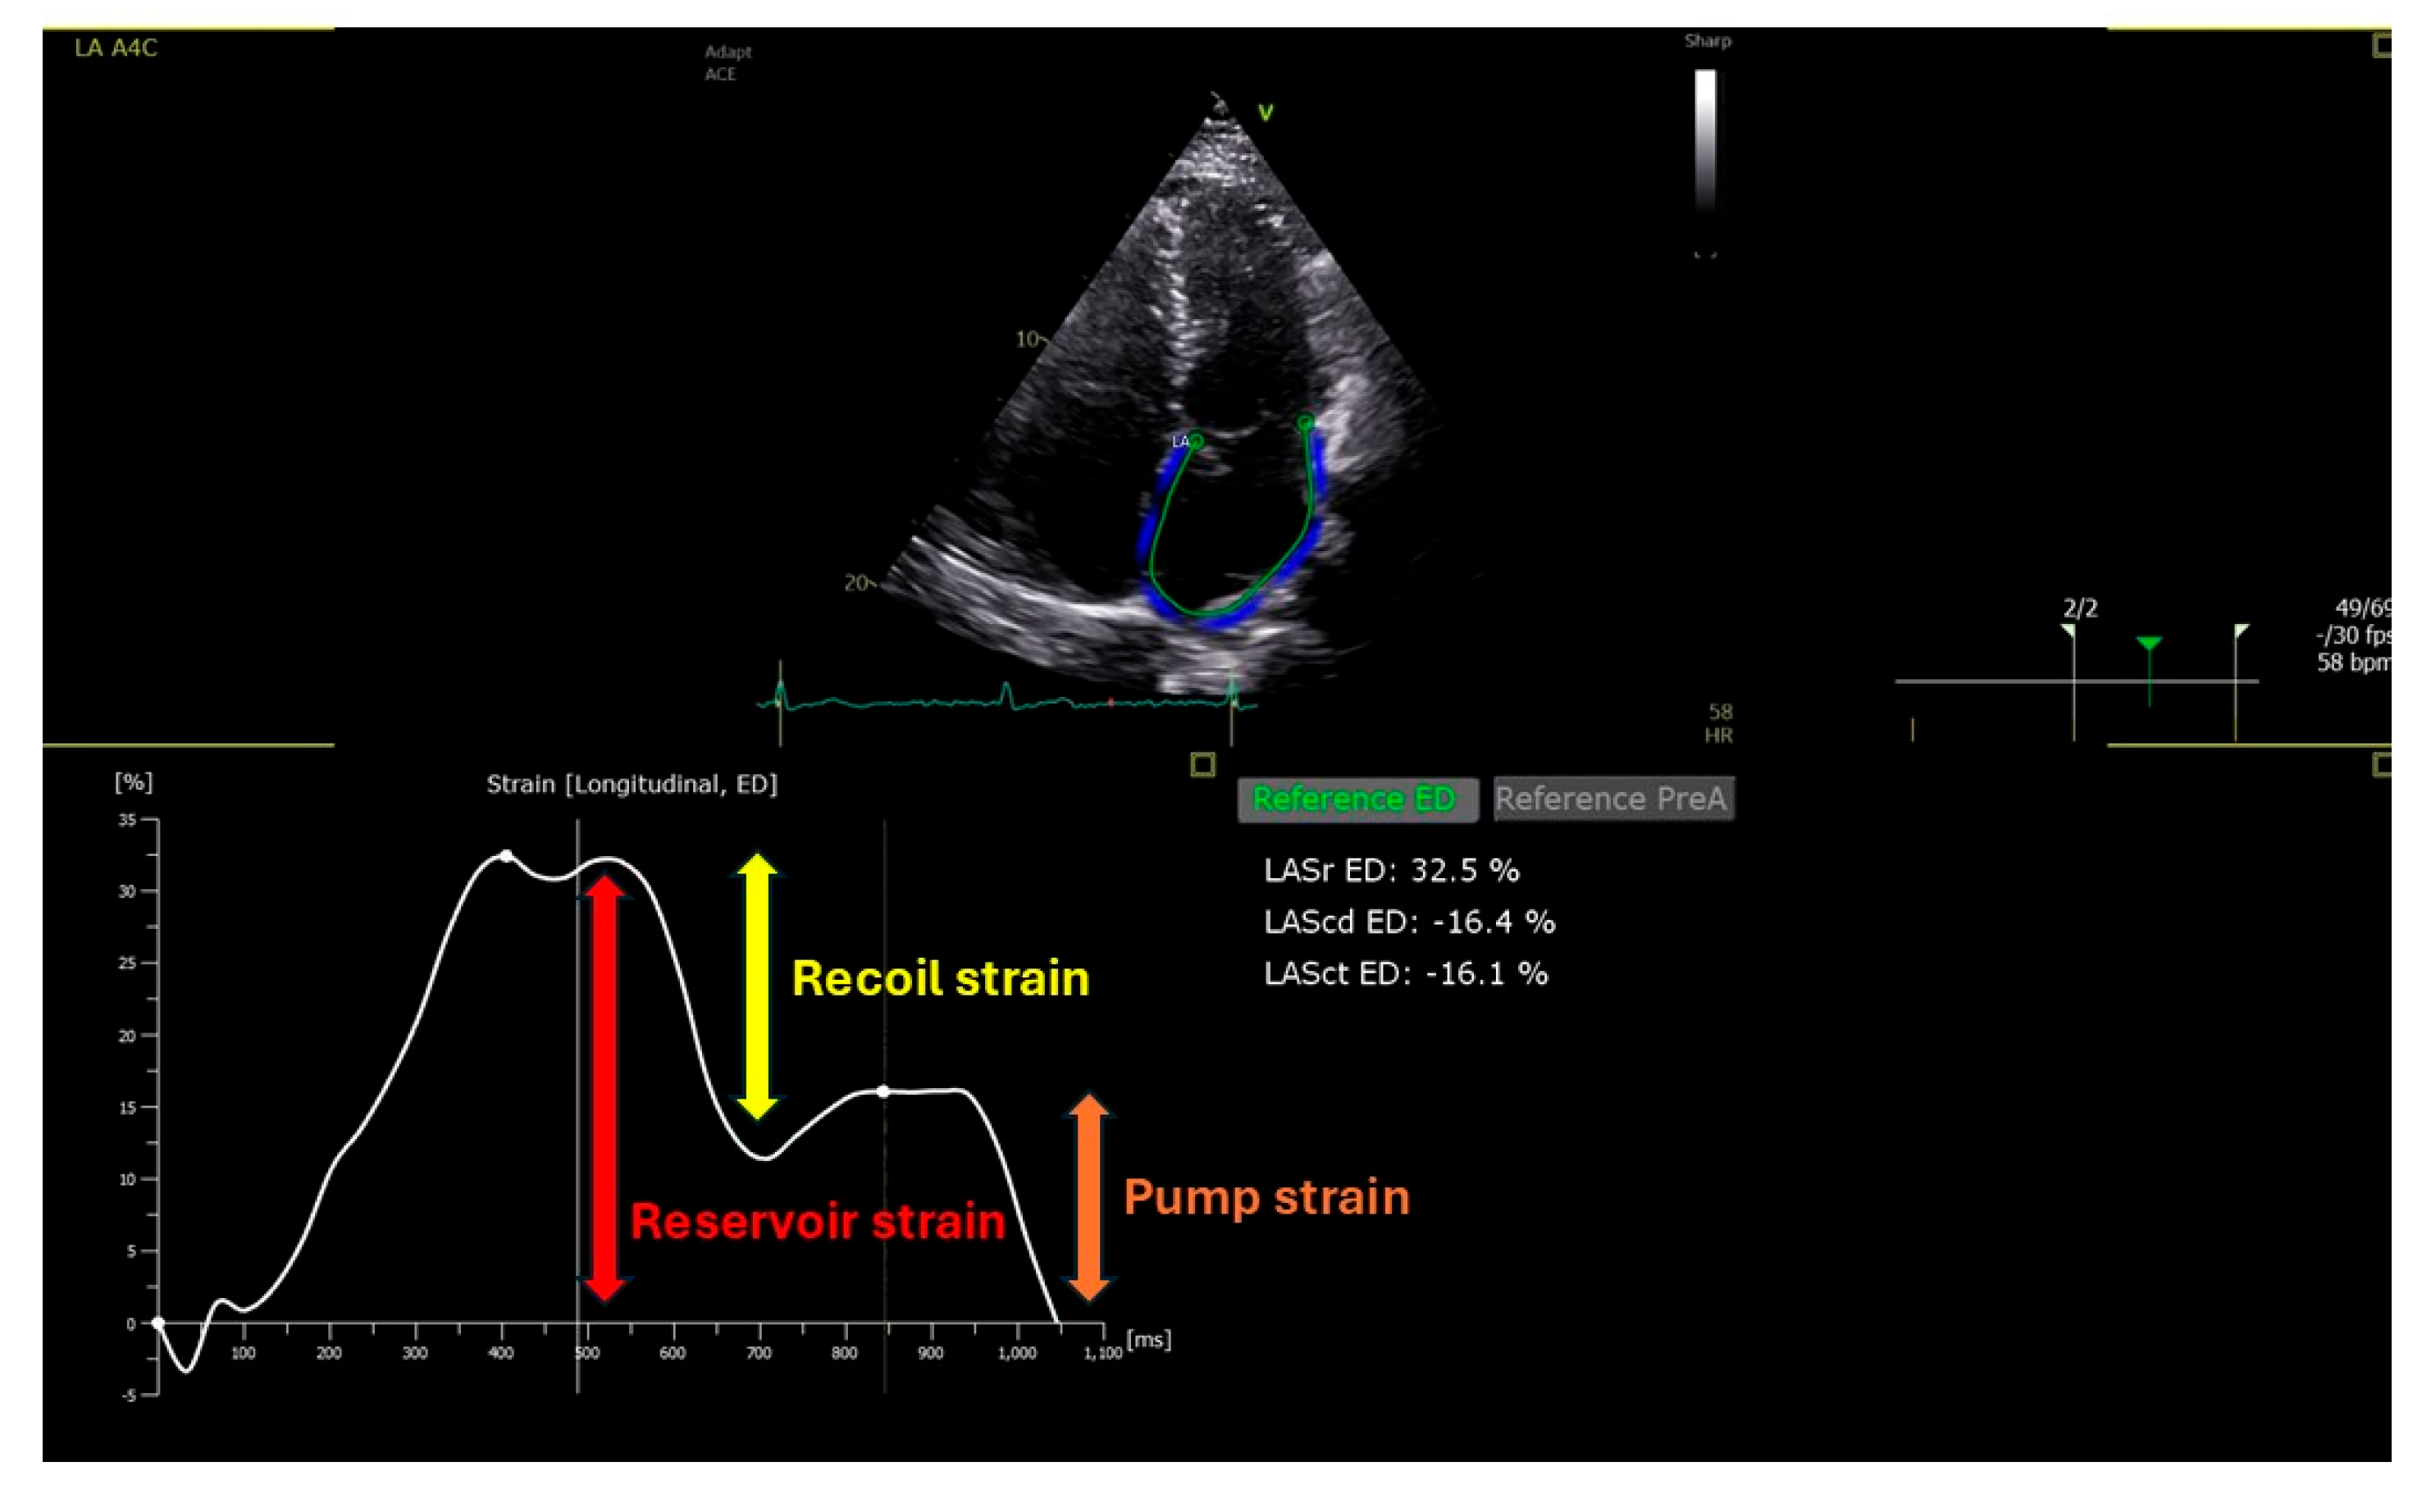

6. Left Atrial Strain (LAS)